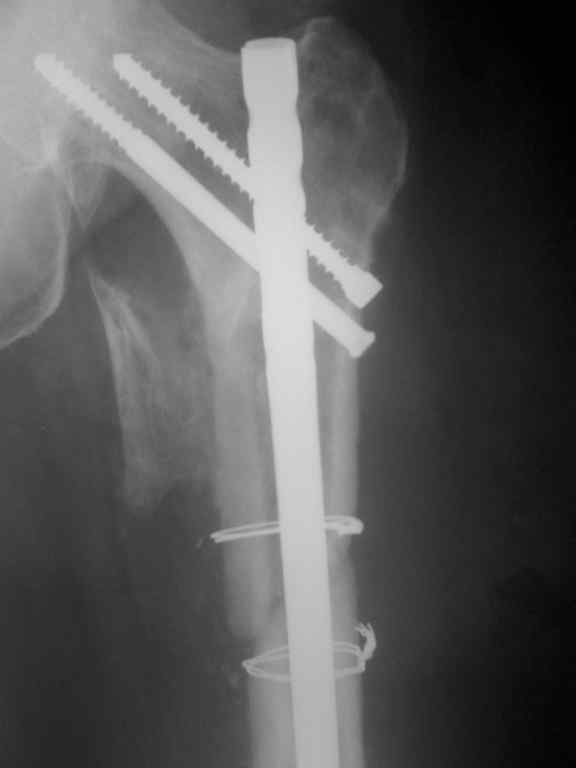

Р-гр после реостеосинтеза

|

Что ж, можно поздравить с успехом, форма бедра отлично восстановлена. Учитывая, что перелом подвертельный, вероятно, достаточно и этого реконструкционного стержня. Не очень понятно, зачем было открываться, и тем более использовать серкляж, но если все получится - победителя не судят.

К сожалению не открывая место перелома выполнить реостеосинтез не представилось возможным т.к канал проксимального отломка полностью закрыт костной тканью. серкляжом фиксирован крупный отломок не видный на Р-гр представляющий собой треть трубки задней поверхности бедренной кости.